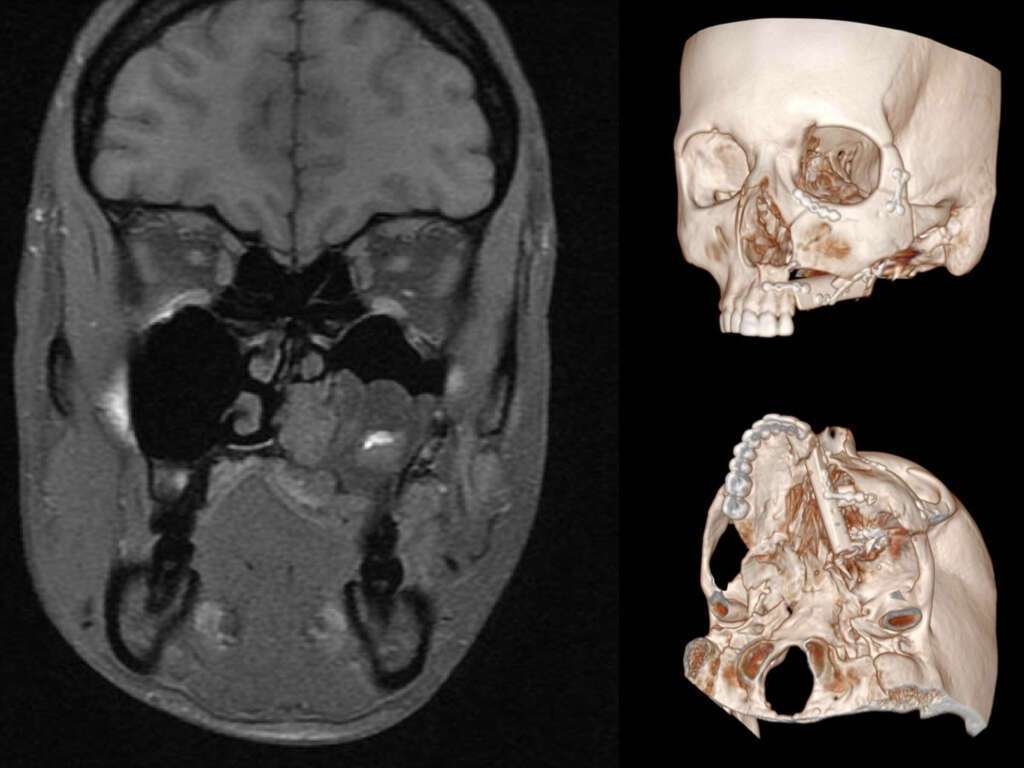

Methods: A previously asymptomatic 25 y.o. female reported her first hemorrhagic episode originated from left upper molar region, with hypovolemic shock, only controlled after embolization. Deformity of the palate, dental mobility and daily epistaxis demanded a second embolization. The deformity worsened after embolization. Arteriography, CT and MRI suggested an AVM, confirmed by biopsy.

A multidisciplinary team defined management by radical resection and immediate reconstruction. A modified facial translocation was performed to allow safe control of the nidus and feeding vessels, preserving the orbital floor and upper portion of the maxilla.

Complete AVM removal included resection of the alveolar bone lateral to the left upper incisors, hard palate, portions of the soft palate, pterygoid region and the left inferior turbinate.